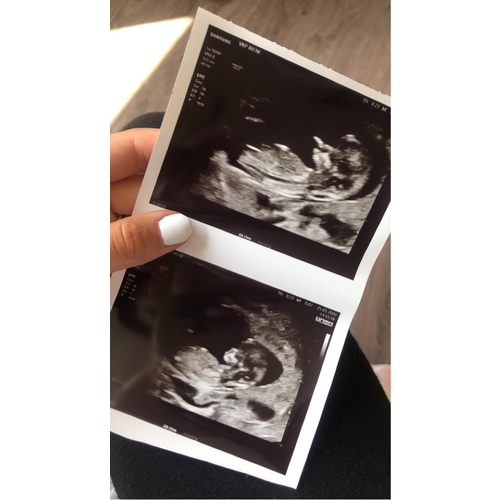

Wilt er iemand mij helpen aub????

Ik kom er echt niet uit 😳 iemand die mij kan helpen?